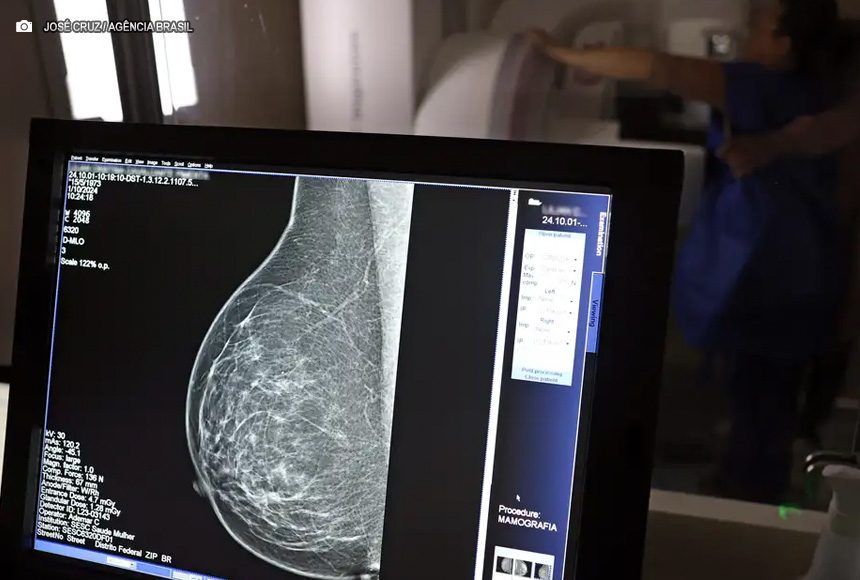

Em junho deste ano, 77.243 brasileiras aguardavam por uma mamografia no Sistema Único de Saúde (SUS). Santa Catarina é o estado com mais mulheres na fila de espera, cerca de 17 mil. Em seguida, aparecem São Paulo (15 mil) e Rio de Janeiro (12,5 mil). Juntos, os três estados somam 56% do total de pacientes à espera do principal exame para detecção do câncer de mama. Os dados foram divulgados nesta quinta-feira (31) pelo Colégio Brasileiro de Radiologia e Diagnóstico por Imagem (CBR).

Segundo a entidade, em alguns locais do país, o tempo de espera por uma mamografia na rede pública pode chegar a 80 dias. O exame, quando realizado em tempo hábil, permite a detecção precoce de alterações mamárias, aumentando as chances de tratamento bem-sucedido e reduzindo a necessidade de intervenções invasivas e onerosas. “Os números revelam parte da sobrecarga no SUS e devem ser levados em conta, especialmente pelos recém-eleitos nas eleições municipais, na formulação e manutenção de políticas de saúde pública”, avaliou o CBR.